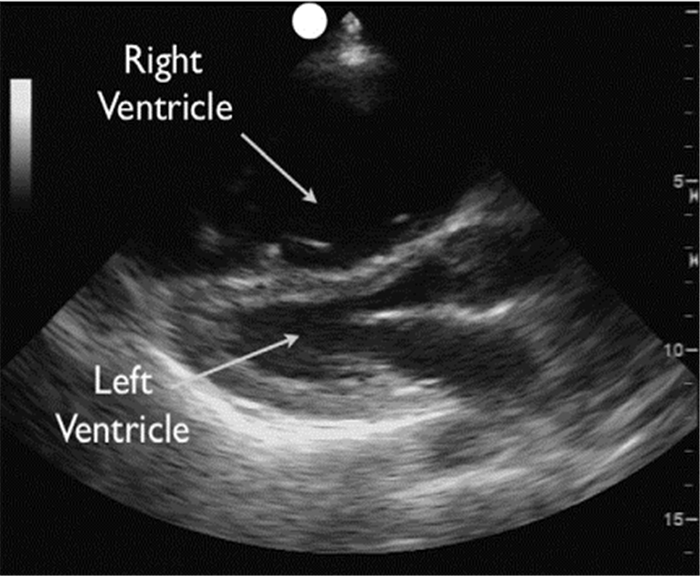

右室扩大、室间隔从右室偏向左室(胸骨旁短轴切面左心室呈“D”型)为肺栓塞间接征象(图 6和图 7),很少能直接在肺动脉主干及左右分支内探及较大栓子这样的直接征象。

| 图 6 胸骨旁左心室长轴:右室压力负荷过重 |

| 图 7 左心室呈“D”型(该图片由华中科技大学同济医学院附属协和医院重症医学科采集) |